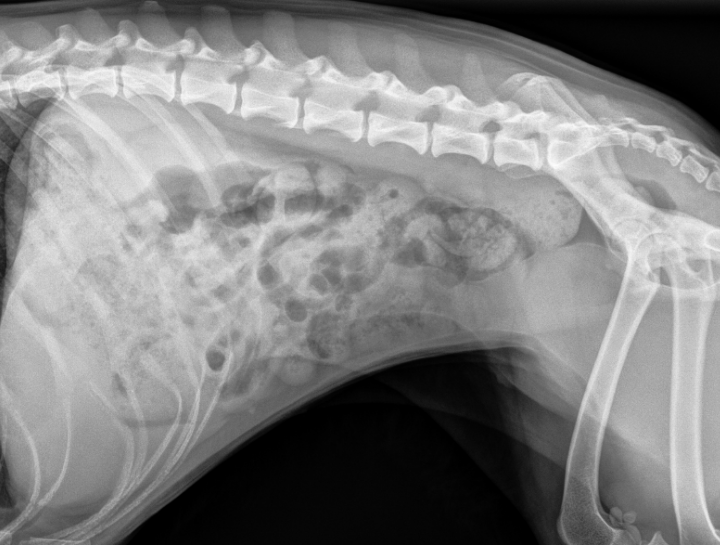

Pet Digital Radiology

Digital x-rays assist in diagnosing illness & injury.